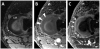

Tissues, such as bone, tendon, and ligaments, contain a high fraction of components with "short" and "ultrashort" transverse relaxation times and therefore have short mean transverse relaxation times. With conventional magnetic resonance imaging (MRI) sequences that employ relatively long echo times (TEs), there is no opportunity to encode the decaying signal of short and ultrashort T2 /T2 * tissues before it has reached zero or near zero. The clinically compatible ultrashort TE (UTE) sequence has been increasingly used to study the musculoskeletal system. This article reviews the UTE sequence as well as various modifications that have been implemented since its introduction. These modifications have been used to improve efficiency or contrast as well as provide quantitative analysis. This article reviews several clinical musculoskeletal applications of UTE.